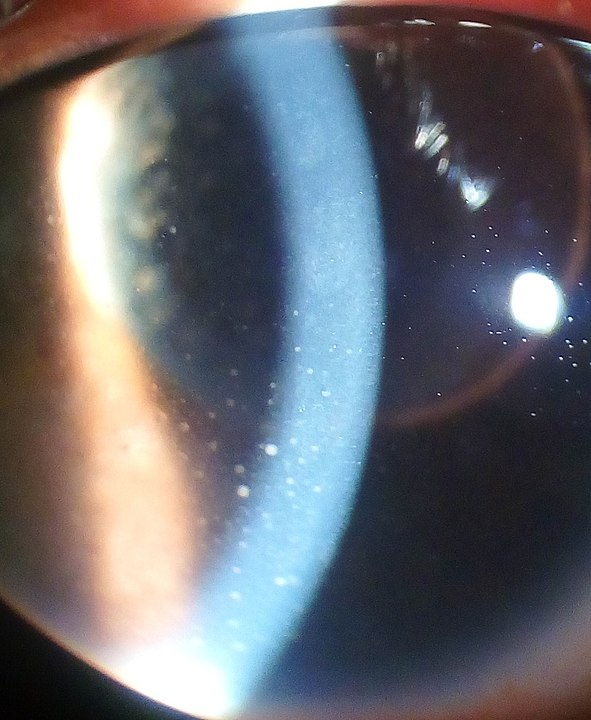

Uveitis is diagnosed with a thorough examination of the eye with a slit lamp microscope and ophthalmoscopy. Visual acuity and intraocular pressure are also evaluated. In some cases, blood work and others tests are required to rule out underlying systemic disease or infection.